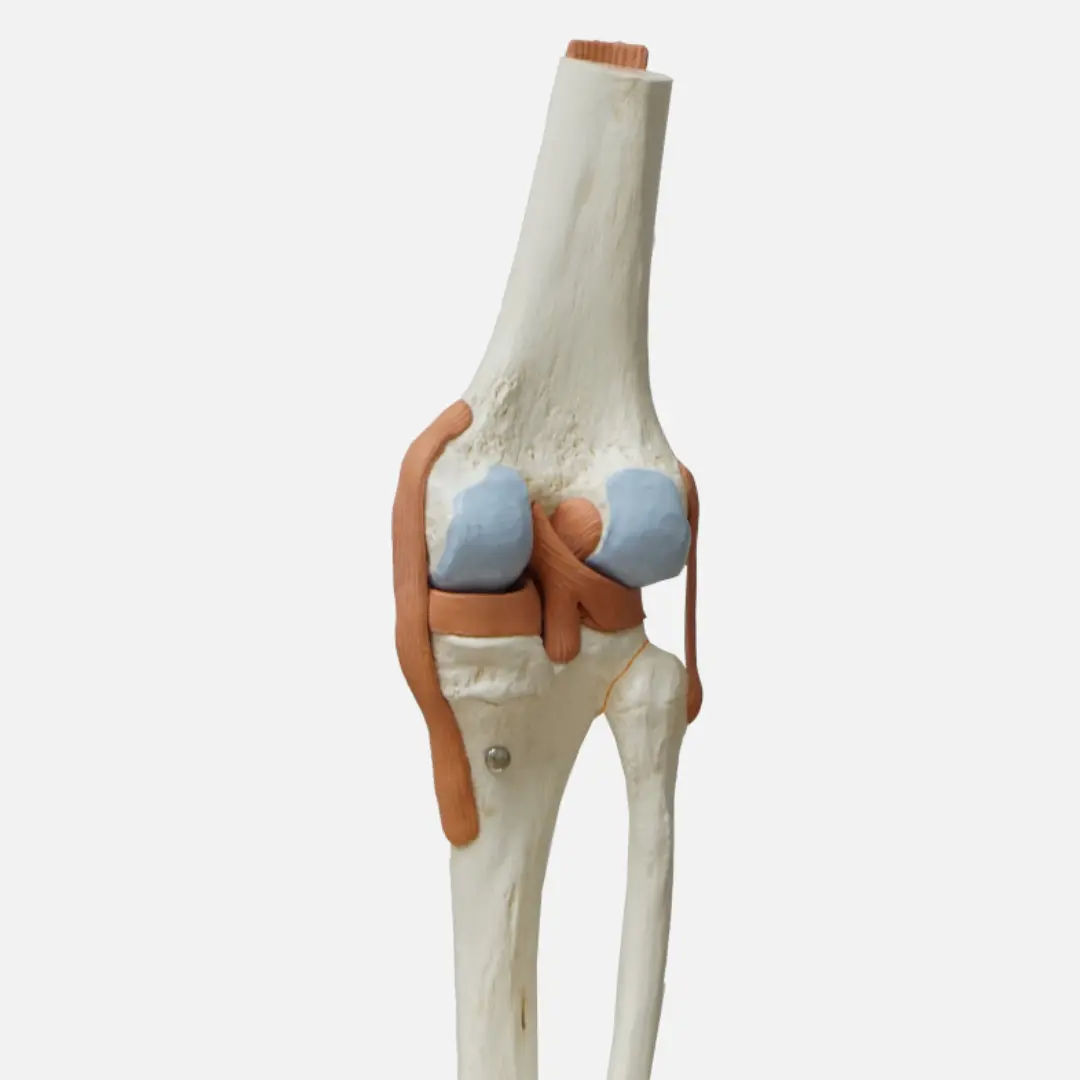

콘드로이친(Chondroitin)은 우리 몸의 연골, 인대, 힘줄, 피부 등 결합 조직에 풍부하게 존재하는 성분입니다. 특히 연골의 주요 구성 성분 중 하나인 프로테오글리칸을 구성하는 핵심 성분이죠. 연골은 관절의 충격을 흡수하고 뼈와 뼈 사이의 마찰을 줄여주는 쿠션 역할을 하는데, 이 연골의 탄력성과 수분 유지를 돕는 것이 바로 콘드로이친입니다.

이처럼 콘드로이친은 관절 건강, 특히 연골의 건강과 기능을 유지하는 데 매우 중요한 역할을 하는 성분입니다.